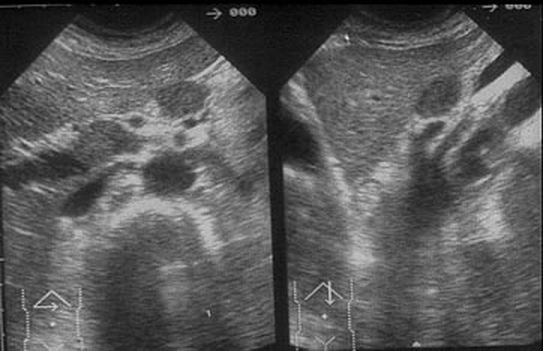

Las adenopatías linfomatosas suelen ser hipoecogénicas, en ocasiones casi anecogénicas, siendo difícil a veces su diferenciación con estructuras vasculares. Weill describió tres patrones ultrasónicos que pueden reconocerse: como una imagen en “panal de abejas”, como una gran masa única de bordes policíclicos y, por último, como una masa envolvente alrededor de la aorta y la cava, en forma de “puño de camisa”.

A nivel de retroperitoneo, pueden metastatizar diferentes carcinomas (mama, pulmón, testículo, hígado...). Las adenopatías metastásicas suelen presentar un patrón más ecogénico que las linfomatosas, lo que permite diferenciarlas bien de las estructuras vasculares.